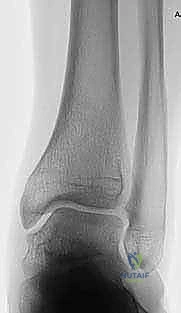

الحالة الثانية: إنقاذ كاحل شابة من الخشونة المبكرة

شابة تبلغ من العمر 28 عاماً، تعاني من تشوه خلقي أدى إلى تركز الوزن على الجانب الخارجي للكاحل، وبدايات تآكل غضروفي. كانت مهددة بدمج الكاحل في سن مبكرة. أجرى لها الدكتور هطيف الجراحة ببراعة، مما أعاد توزيع الوزن بشكل مثالي، وأنقذ مفصلها الطبيعي، وعادت لممارسة حياتها الطبيعية بثقة عالية.

- المرحلة الثانية (الأسابيع 3 - 6): بدء تمارين المدى الحركي (تحريك الكاحل لأعلى وأسفل) لمنع التيبس. يتم متابعة التئام العظم بالأشعة.

- المرحلة الثالثة (الأسابيع 6 - 12): بمجرد ظهور علامات التئام العظم في الأشعة، يُسمح بالتحميل الجزئي للوزن تدريجياً، وصولاً إلى التحميل الكامل. تبدأ تمارين تقوية العضلات المحيطة بالكاحل.